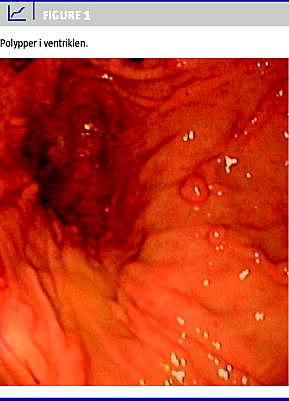

Ved øvrige undersøgelser blev der fundet steatoré, vurderet ved tre døgns opsamling af fæces, der blev undersøgt for volumen og fedt (38,8 mmol alifatisk carboxylat/døgn), malabsorption af zink, K- og svær D-vitamin-mangel samt anæmi ved kronisk sygdom. En ultralydundersøgelse af abdomen viste let hepatosplenomegali, kolecystolitiasis og højresidig nefrolitiasis. En øsofagogastroduodenoskopi viste polypper i ventriklen (Figur 1 ) samt blødning af nyere og ældre dato, hvilket blev tolket som værende udløst af epistaxis, idet der ikke blev påvist nogen blødningskilde. En computertomografisk kolografi viste splenomegali. Der blev ikke gjort noget fund ved coeliacusprøver, fæcesdyrkning, sigmoideoskopi, kapselendoskopi, magnetisk resonans-skanning af tyndtarm og dexa-skanning. Efter patientens ønske blev der ikke udført koloskopi.

De diagnostiske overvejelser rettede sig mod malabsorptionstilstande, herunder pancreaslidelse; patienten var dog ikke smerteplaget. Fundet af polypper i ventriklen sammenholdt med hud- og negleforandringer og hårtab gjorde, at patienten efter en måneds indlæggelse blev diagnosticeret med CCS. Behandling med symptomatisk substitutionsterapi og prednisolon resulterede i bedring af de biokemiske forhold og almentilstanden samt normalisering af afføringsmønsteret.